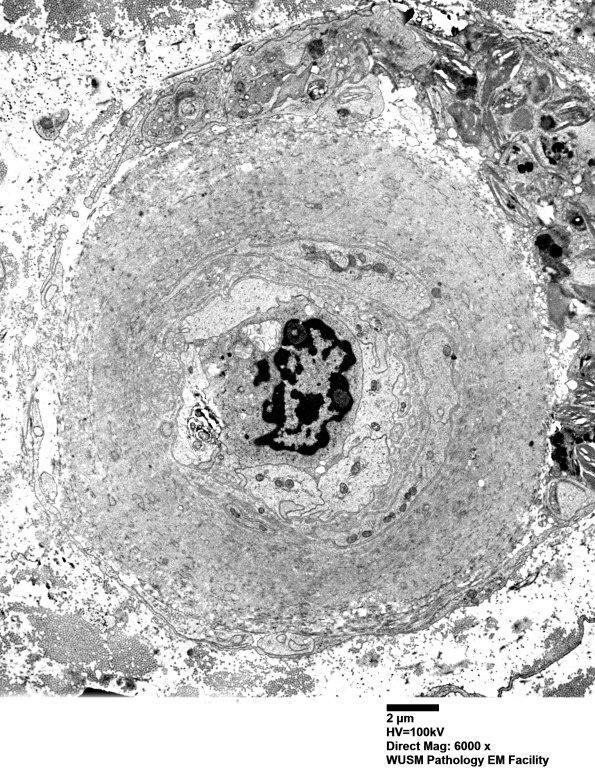

Washington University Experience | VASCULAR | Hypoxia-Ischemia, fetal-neonatal | White Matter | 5C1 (Case 5) EM014 - Copy

5C1 (Case 5) EM014 - Copy